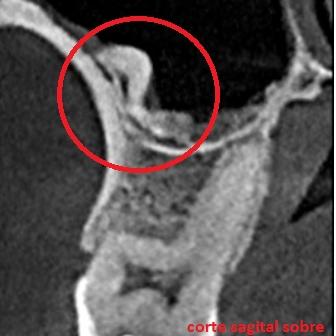

La presentación de casos radiográficos, permite la visualización de patologías que son muy difíciles de ver en la clínica, ya que muchos de ellos son hallazgos radiográficos. Además permite ver y refrescar clasificaciones y conceptos muchas veces estudiados. La presentación de los mismos no incluyen datos personales, mas que edad y sexo, que suelen ser importantes para ver la correlación entre la patología, su aparición o forma de presentación.